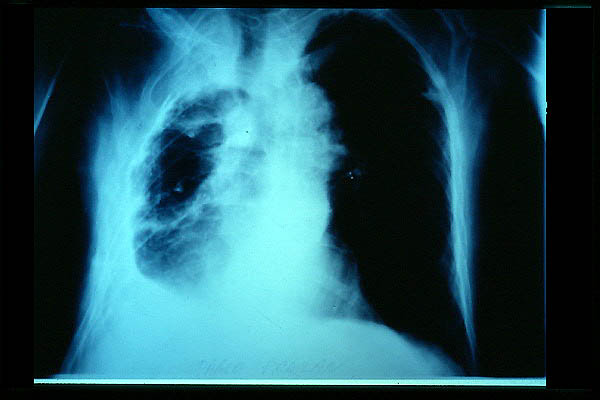

Tumoración mediastínica